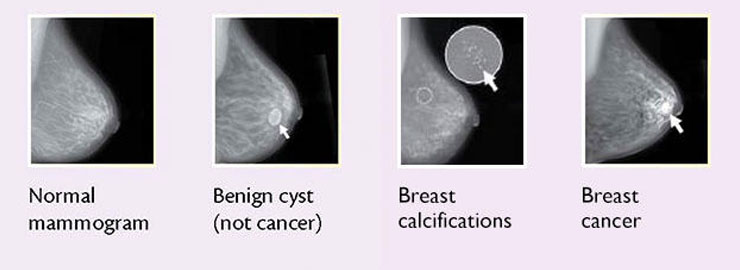

Breast cysts: Fluid-filled sacs form when fluid becomes trapped in the milk ducts. Cysts are common in premenopausal women.

Breast cancer: A tumor growing in the breast tissue causes a lump.